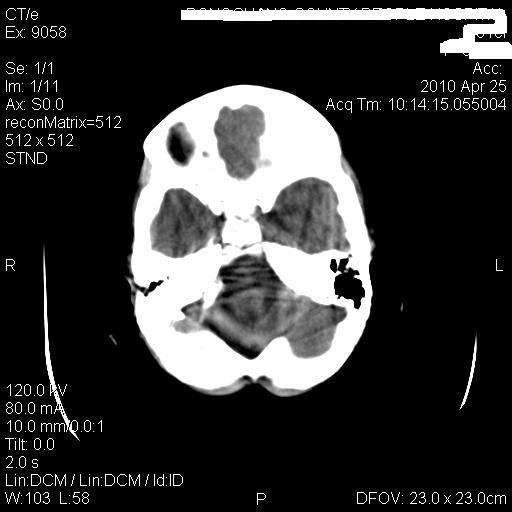

标题: PED3218:3岁女孩,曾有外伤史。未提供前片 [打印本页]

标题: PED3218:3岁女孩,曾有外伤史。未提供前片

发育略有障碍。欢迎大家发言。谢谢!

考虑右侧额顶叶脑软化灶并脑穿通畸形。

考虑:1)右侧额顶叶脑软化灶并脑穿通畸形。2)胼胝体发育不良。

支持考虑:1)右侧额顶叶脑软化灶并脑穿通畸形。2)胼胝体发育不良。

1)右侧额顶叶脑软化灶。2)胼胝体发育不良?

考虑右侧额顶叶软化灶并脑穿通畸形,胼胝体发育不全。

还有脑室周围白质软化症